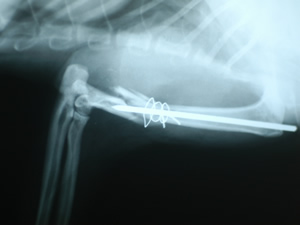

猫の上腕骨骨折の再手術

1)この症例は猫の上腕骨の骨折です。

2)ピンとワイヤーで固定されていますが、ピンの挿入が不充分です。

3)3日後にピンが抜け再骨折し他院より転院した症例です。

4)全てのピンとワイヤーは抜去され、プレート固定が施され、1カ月後には完治しました。